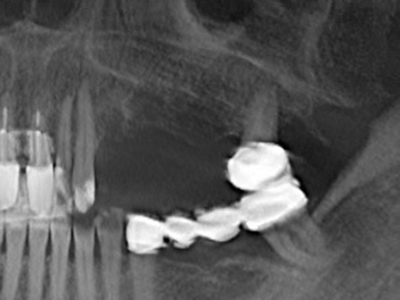

Bei der Knochenblockentnahme zeigen sich weitere Vorteile für die Piezochirurgie: Neben der bereits beschriebenen hohen Präzision bei der Osteotomie stellt sich gerade die Verwendung der dünnen Sägespitzen als besonders materialschonend heraus. Bei der Verwendung insbesondere von Lindemannfräsen sind mit deutlich höheren Entnahmeverlusten durch die dickere Instrumentenspitze zu rechnen (Lakshmiganthan, Gokulanathan et al. 2012). Die insbesondere bei retromolar entnommenen Blocktransplantaten notwendige basale Abtrennung wird durch speziell hierfür vorgesehene rechtwinklige Sägen erleichtert, so dass die Piezochirurgie als präzises, übersichtliches und sicheres Verfahren zur retromolaren Knochenblockgewinnung angesehen wird (Happe 2007) (Abb. 1-12).

Sollen chirurgische Eingriffe mit unmittelbarer Knochenbeziehung an empfindlichen Strukturen wie Blutgefäßen oder Nerven erfolgen, so bergen rotierende Instrumente ein erhebliches Potential an iatrogener Schädigung. Gerade bei Nervdarstellungen nach iatrogener Schädigung, oder aber im Zuge einer Nervlateralisation für resektive und rekonstruktive Eingriffe oder Implantatinsertionen können piezoelektronische Geräte hilfreich sein Knochendeckel zu präparieren und nervnahe Hartgewebsanteile zu entfernen (Abb. 17-20). Ein leichter Kontakt des Nervstrangs zur Piezospitze bleibt dabei in der Regel folgenlos – allerdings kann eine unvorsichtige Vorgehensweise mit sägeartigen Bewegungen bzw. Ansätzen bei noch vorhandener knöcherner Unterlage durchaus temporäre oder aber auch permanente Nervschädigungen verursachen. Das Risiko einer solchen Schädigung wird jedoch als wesentliche geringer eingeschätzt als unter Anwendung von Säge- oder Fräsinstrumenten (Pereira, Gealh et al. 2014).